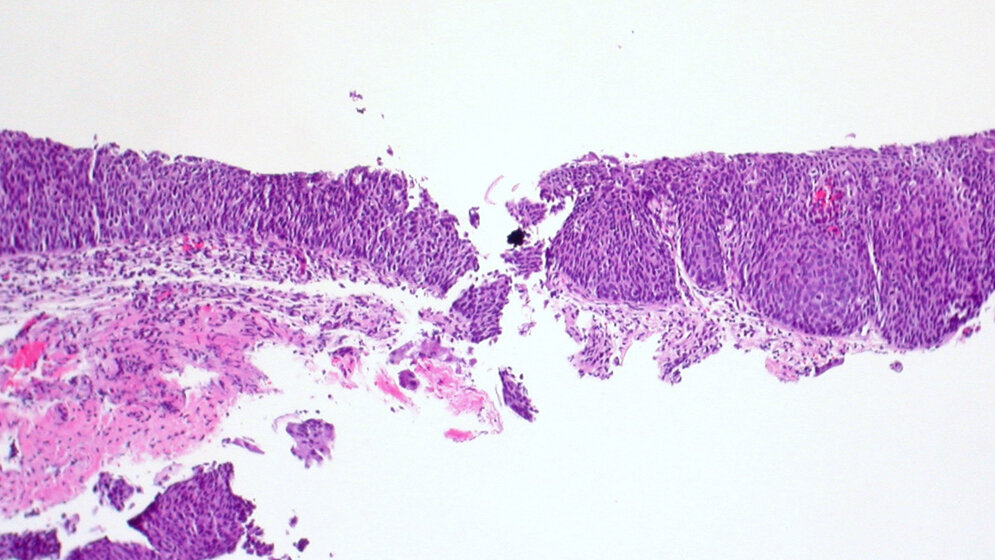

Jedes Jahr erkranken in Deutschland circa 4.500 Frauen an Gebärmutterhalskrebs (Zervixkarzinom), die meisten erhalten die Diagnose im Alter zwischen 40 und 59 Jahren. In circa 90% der Fälle wird dieser Krebs durch eine Infektion mit HP-Viren (Humane Papillomviren) ausgelöst. Die prophylaktische Impfung gegen die auslösenden HP-Viren wird daher für alle Kinder bzw. Jugendlichen (auch für die Jungen!) im Alter von 9-14 Jahren empfohlen und ist eine Kassenleistung. Die Virusübertragung erfolgt über die Mund- und Genitalschleimhaut. Durch die Früherkennungsuntersuchung beim Frauenarzt werden Krebsvorstufen und Frühformen oft schon im Alter von 20-40 Jahren entdeckt und sind dann in der Regel heilbar. Bei einem in das Gewebe bereits eingewachsenen (invasiven) Zervixkarzinom liegt die 5-Jahres-Überlebensrate auch noch bei circa 69%, was bedeutet, dass fünf Jahre nach Diagnose dieser Spätstadien fast 7 von 10 Patientinnen noch leben [2].